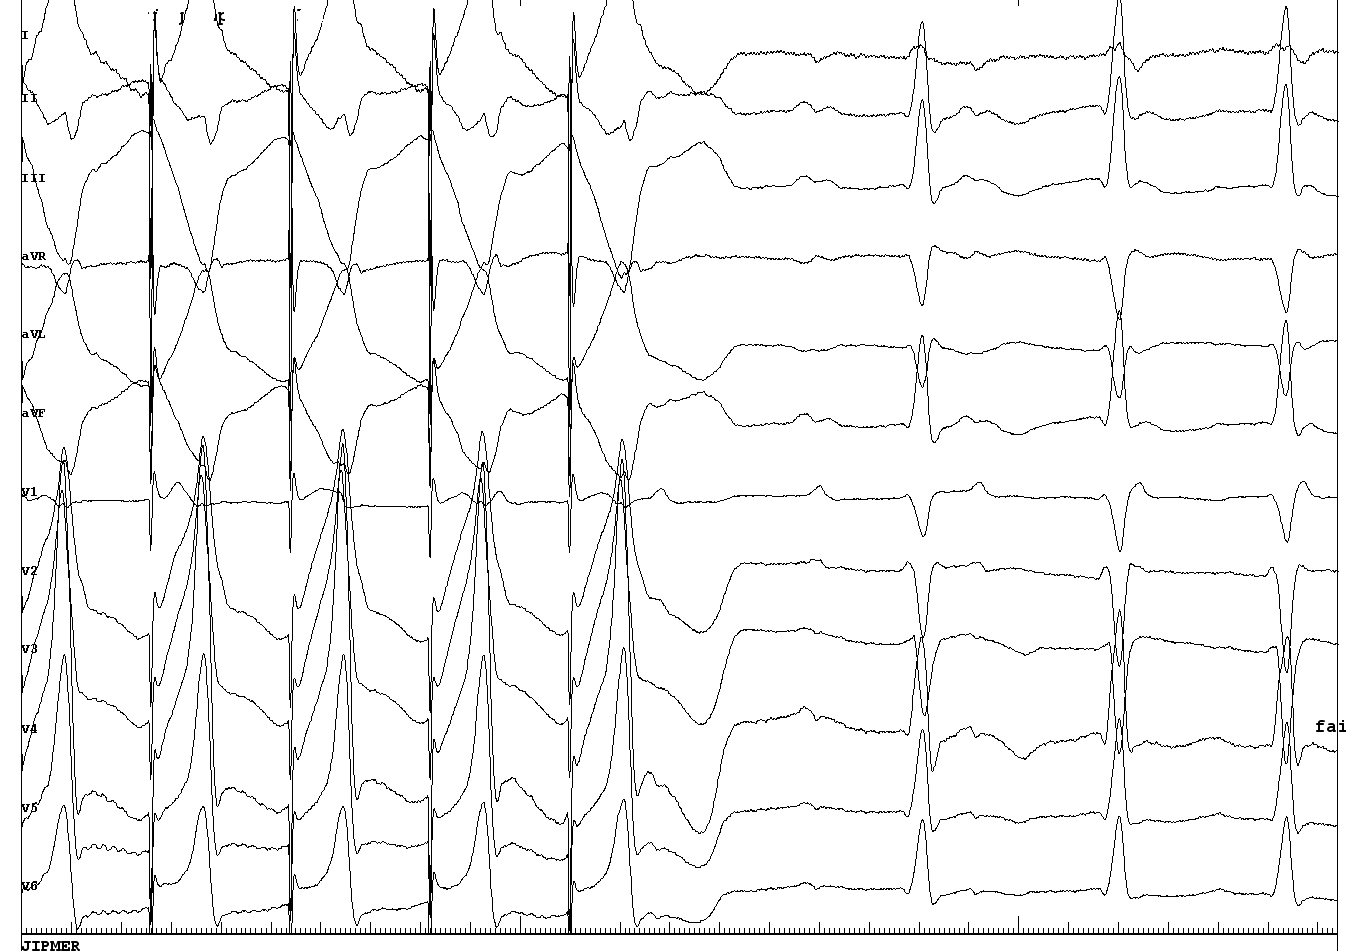

meherunissa.png

P wave in relation to reference

komala_p_wave.JPG

komala_p_wave_measurements.JPG